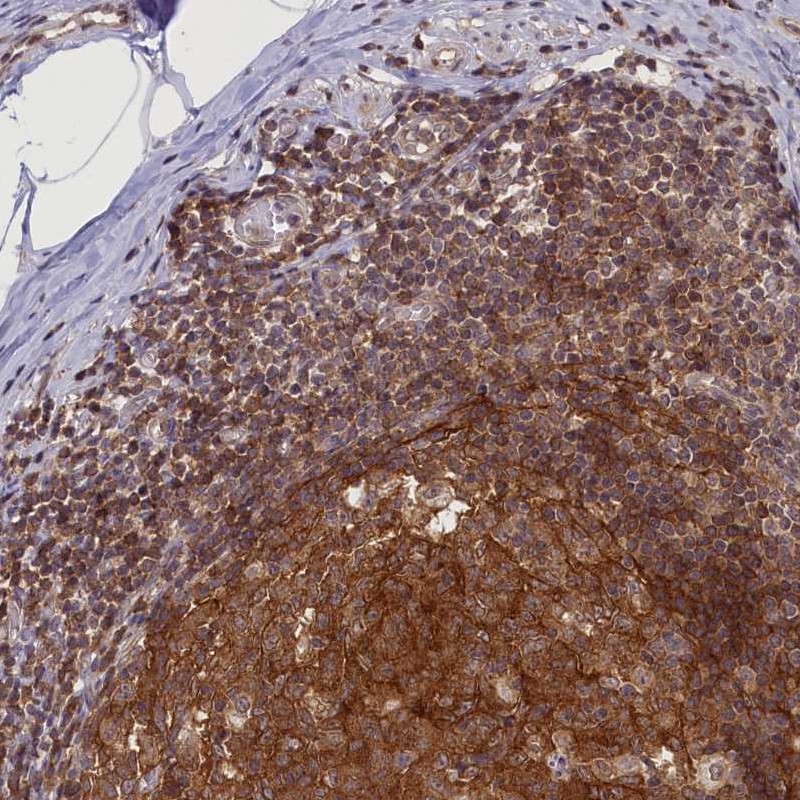

Immunohistochemical staining of human appendix shows strong cytoplasmic positivity in lymphoid tissue.